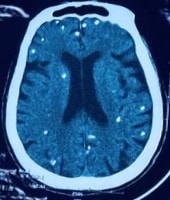

Người phụ nữ 77 tuổi được chuyển lên từ tuyến trước vì rối loạn ý thức đe dọa suy hô hấp, hình ảnh cắt lớp vi tính sọ não và X-quang ngực cho thấy rất nhiều nốt cản quang trong nhu mô não và dưới da vùng ngực-bụng.

Người bệnh được chuyển lên từ tuyến trước vì rối loạn ý thức đe dọa suy hô hấp, hình ảnh cắt lớp vi tính sọ não và X-quang ngực cho thấy rất nhiều nốt cản quang trong nhu mô não và dưới da vùng ngực-bụng.

Mặc dù xét nghiệm kháng thể IgM với sán dây lợn âm tính, các tổn thương trên X-quang gợi ý người bệnh trước đây bị nhiễm ấu trùng sán dây lợn, sau đó các nang sán trở nên vôi hóa và tồn tại lâu dài trong tổ chức. Người bệnh được điều trị theo phác đồ bệnh chính, đáp ứng và ra viện tiếp tục điều trị theo tuyến.

Nang sán dây lợn có thể tự thoái hóa hoặc bị vôi hóa, tạo nên nhiều hình ảnh cản quang phát hiện được trên phim X-quang như trường hợp bệnh nhân trên.